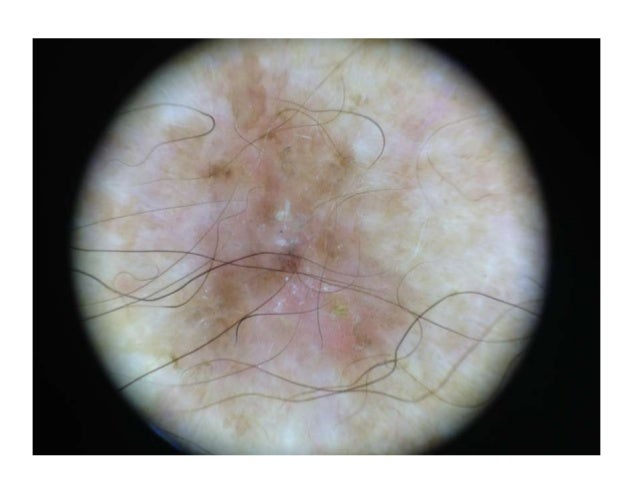

Bowens disease, Pigmented By H. Kittler - YouTube